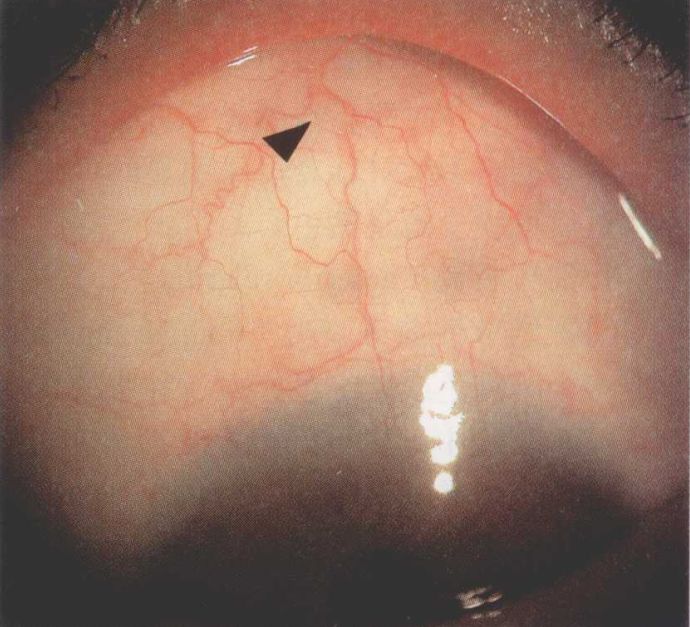

红血丝相对斑的问题就高发多了,它也是普通健康人群里最影响巩膜白净程度的原因。红血丝看起来是巩膜(眼白)的问题,但它其实并没有长在巩膜上,而是长在结膜上,结膜就是覆盖在巩膜上的那层透明组织。

正常情况下,结膜的血管就像扁扁的透明管子一样,透过结膜可以看到白色巩膜,但是当遇到细菌、病毒或理化等因素入侵刺激时,血管就会受炎性因子的刺激的扩张,血液会涌入原来中空扁塌的血管,形成血丝。